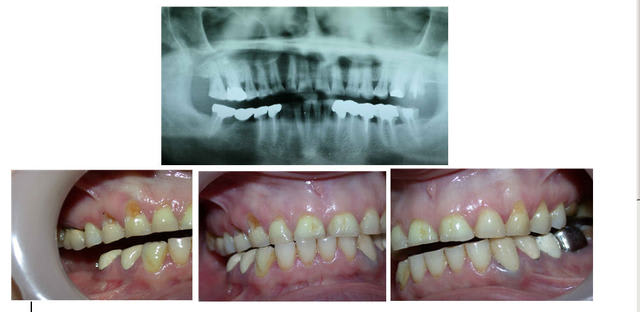

l'atteinte coronaire était telle que l'on voyait la pulpe par transparence ....

au passage en comparant photo initiale et celle ci après réalisation prothétique le recentrage des milieux est presque bien...

Je crois que sans le faire exprés, tu as présenté deux photos la 1 et la 2, dans le premier post qui semblent representer les latéralités gauche et droite.

comme on le voit la lateralité droite est facile et la gauche, beaucoup plus importante dans le désengrénement.

Ce qui fait penser aux AFMP de Planas et qui fait comprendre qu'une mastication préférentielle à droite depuis longtemps, a conduit à un dévellopement plus important du max sup droite qui explique le decentrage des points interincisifs.

si on compare photo initale en occlusion la patiente est presque en articulé croisé alors qu'avec la photo du bridge conventionnel en occlusion on a vraiment une impression d'un réel recul mandibulaire que nous n'aurions pas obtenu en augmentant de façon simple la DV sur la tige incisive et c'est pour cette raison que je pense réellement que l'on a obtenu un fonctionnement en RC.